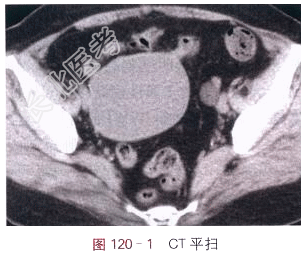

- [材料题] 女,78岁,自觉腹部肿块3月余。体格检查:右下腹肿块,边界清,质地软。影像学资料如图120-1~图120-2所示。

读片分析:右侧附件区见直径8cm类圆形囊性灶,密度均匀,囊内未见分隔;囊壁薄,未见壁结节,未见异常强化。左侧附件区也见直径1.5cm类圆形囊性灶,密度均匀,未见强化。